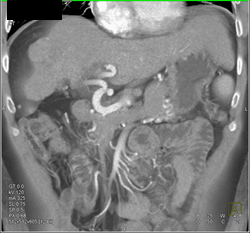

Diagnosis

Intraductal Papillary Mucinous Neoplasm (IPMN)